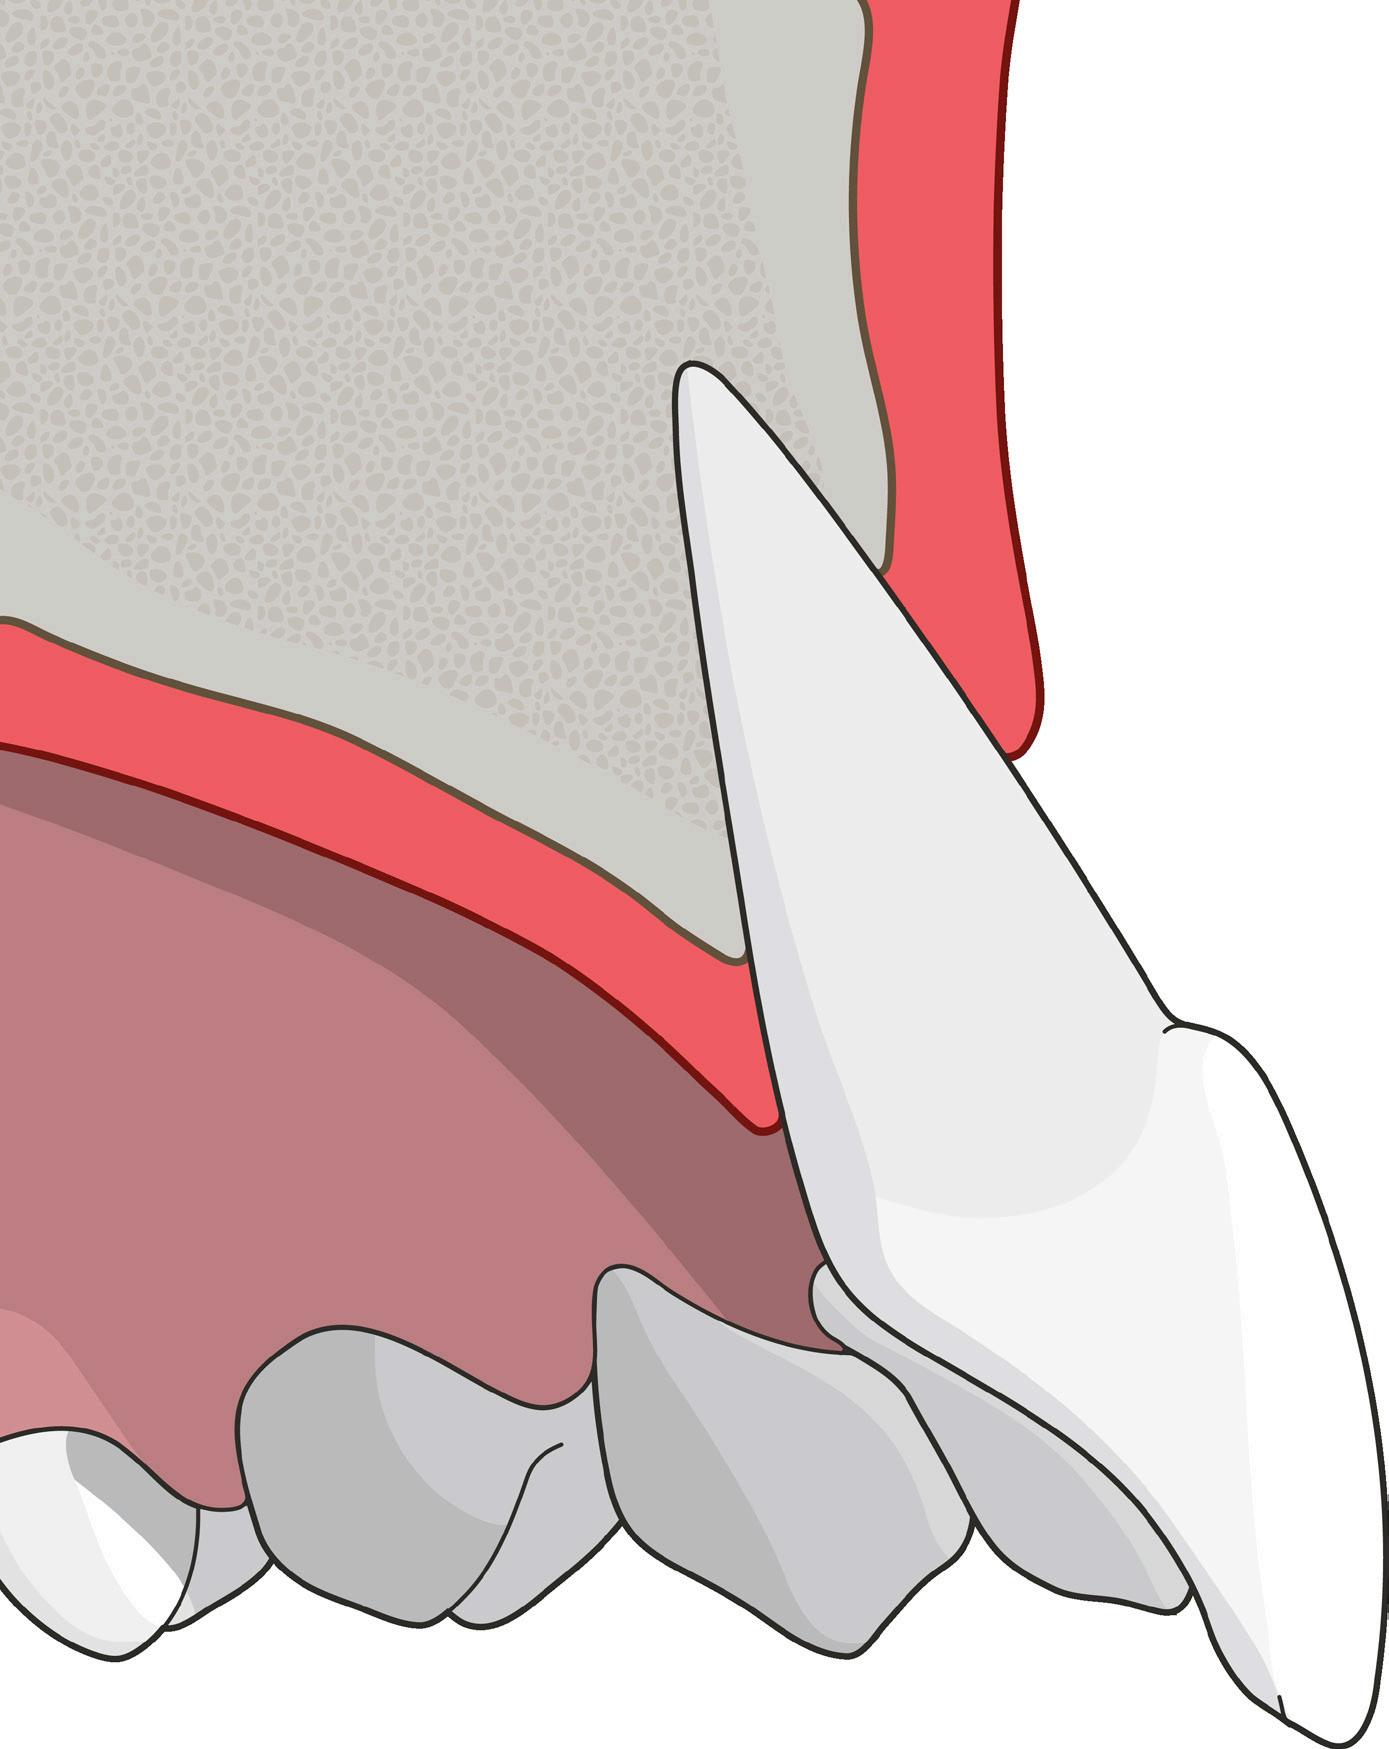

Cuando se trata de salvar los dientes, el éxito clínico depende en gran medida de los tratamientos periodontales y endo dónticos.1 De hecho, los dientes que se pierden durante el tratamiento perio dontal y los llamados «dientes insalva bles» suelen presentar problemas endo dónticos.

En los tratamientos endodónticos no quirúrgicos, los dentistas eliminan cui dadosamente la caries, la pulpa infla mada o infectada, limpian, desinfectan y conforman los conductos radiculares, y colocan una obturación para sellar el conducto. La tasa de éxito de este tra tamiento es menor cuando las lesiones

periapicales son extensas. En estos ca sos, el tratamiento endodóntico quirúr gico es una alternativa.

Las lesiones periapicales se encuentran entre las lesiones patológicas más comu nes en el hueso alveolar.2 Este tipo de le siones provoca defectos óseos y, cuando son grandes, el organismo no es capaz de regenerar hueso nuevo para rellenar los. Entonces el tejido conectivo invade el defecto óseo y afecta a los resultados clínicos.3

Los endodoncistas deberían diagnosti car la situación clínica, incluido el acceso al conducto, la ubicación y la anatomía de los dientes y de los tejidos circundan tes, y en caso de recidiva, la calidad del tratamiento endodóntico más reciente. Solo así es posible hacer un tratamien to no quirúrgico o quirúrgico apropiado.

Microcirugía periapical regene rativa

La microcirugía periapical regenerativa emplea los principios fundamentales de la endodoncia, la periodoncia y la odonto logía oral y restauradora. Por lo general, el objetivo del tratamiento es eliminar todos los posibles factores causantes de lesio nes periapicales, reparar la arquitectura del tejido periapical perdido y conservar la estructura y la anatomía de la raíz y de los tejidos blandos. También es importan te prevenir la recidiva de la enfermedad a largo plazo.